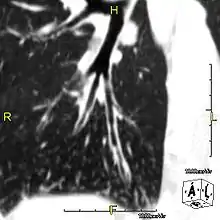

Primary ciliary dyskinesia (PCD) is a rare, autosomal recessive genetic ciliopathy, that causes defects in the action of cilia lining the upper and lower respiratory tract, sinuses, Eustachian tube, middle ear, Fallopian tube, and flagella of sperm cells. The alternative name of "immotile ciliary syndrome" is no longer favored as the cilia do have movement, but are merely inefficient or unsynchronized. When accompanied by situs inversus the condition is known as Kartagener syndrome.[1]

Around 80% of people with primary ciliary dyskinesia experience respiratory problems beginning within a day of birth. Many have a collapsed lobe of the lung and blood oxygen low enough to require treatment with supplemental oxygen.[3] Within the first few months of life, most develop a chronic mucus-producing cough and runny nose.[3] The main consequence of impaired ciliary function is reduced or absent mucus clearance from the lungs, and susceptibility to chronic recurrent respiratory infections, including sinusitis, bronchitis, pneumonia, and otitis media. Progressive damage to the respiratory system is common, including progressive bronchiectasis beginning in early childhood, and sinus disease (sometimes becoming severe in adults). However, diagnosis is often missed early in life despite the characteristic signs and symptoms.[4] In males, immotility of sperm can lead to infertility, although conception remains possible through the use of in vitro fertilization, there also are reported cases where sperm were able to move.[5] Trials have also shown that there is a marked reduction in fertility in females with Kartagener's syndrome due to dysfunction of the oviductal cilia.[6]

Many affected individuals experience hearing loss and show symptoms of otitis media which demonstrates variable responsiveness to the insertion of myringotomy tubes or grommets. Some patients have a poor sense of smell, which is believed to accompany high mucus production in the sinuses (although others report normal – or even acute – sensitivity to smell and taste). Clinical progression of the disease is variable, with lung transplantation required in severe cases. Susceptibility to infections can be drastically reduced by an early diagnosis. Treatment with various chest physiotherapy techniques has been observed to reduce the incidence of lung infection and to slow the progression of bronchiectasis dramatically. Aggressive treatment of sinus disease beginning at an early age is believed to slow long-term sinus damage (although this has not yet been adequately documented). Aggressive measures to enhance clearance of mucus, prevent respiratory infections, and treat bacterial superinfections have been observed to slow lung-disease progression. The predicted incidence is 1 in approximately 7500.[7]

When accompanied by the combination of situs inversus (reversal of the internal organs), chronic sinusitis, and bronchiectasis, it is known as Kartagener syndrome[1] (only 50% of primary ciliary dyskinesia cases include situs inversus).